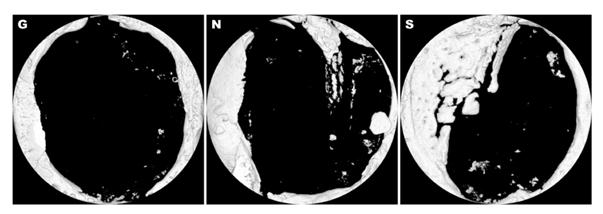

µ¿¹° ¸ðµ¨ÀÇ °ñ ¼Õ½Ç ºÎÀ§¿¡ ¼¼¸®½Å ´Ü¹éÁúÀ» Á©¶óƾ¿¡ Èí½À½ÃÄÑ ºÎÂø½Ã۰í 8ÁÖÈÄ¿¡ MicroCT ÃÔ¿µÀ» ÁøÇàÇß´Ù. »çÁø G: Á©¶óƾ 󸮱º, »çÁø N: ¹Ì󸮱º, »çÁø S: ¼¼¸®½Å+Á©¶óƾ 󸮱º.

¿¬±¸ÁøÀÌ ´ç´¢º´ ¸ðµ¨ ½ÇÇ赿¹°¿¡ ¼¼¸®½ÅÀ» ¹ß¶óÁØ °á°ú, »À ºÎÇÇ´Â ¼¼¸®½ÅÀ» ó¸®ÇÏÁö ¾ÊÀº ½ÇÇ豺º¸´Ù 3¹è Áõ°¡ÇÑ 3.8§§À¸·Î È®ÀεƴÙ.

½ÇÇè¿¡ »ç¿ëÇÑ Á¶Á÷À» ºÐ¼®Çغ¸´Ï »õ·Î »ý±ä »ÀÀÇ »ý¼º·üÀº ´ëÁ¶±ºº¸´Ù 6.6¹è Áõ°¡ÇÑ 8.3%¿´´Ù.